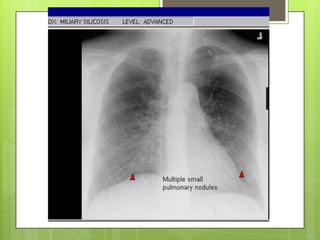

CLÍNICA  Datos clínicosno son específicos.  Formas leves no causan síntomas  En etapas avanzadas: tos (primero) y disnea Rx tórax:  Formas simples nódulos redondeados densos de 1.5-10 mm en campos pulmonares superiores  Formas complicadas: lesiones > 10 mm en uno a dos tercios del pulmón. Calcificación de ganglios en “cascara de huevo” ocurre en 5%

DIAGNÓSTICO  Exposición laboral>5 años  Radiografía con imágenes compatibles